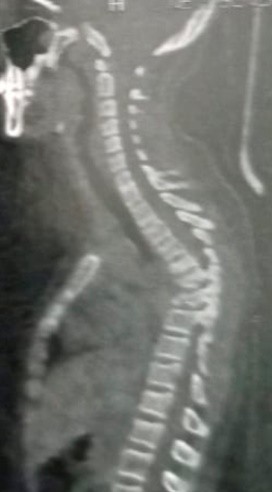

A case of kyphosis in the thoracic vertebrae of a girl at the age of ten years. The convexity was in the upper part of the thoracic vertebrae. It was caused by the impact of a solid body falling from the top of a house on the girl while she was passing under the house. This impact resulted in compression and fusion of a number of thoracic vertebrae, which led to a very, very high hunching angle, as is evident in the CT scan and MRI. Immediately after the patient was diagnosed, she was prepared for surgery to correct the deformity resulting from the kyphosis and to relieve pressure on the neural canal in the thoracic vertebrae. By the grace of God and His grace, the Almighty, the daughter was born safely to her family. The CT scan and the normal follow-up were very, very beautiful, as it was clear that the full correction of the angle of hump to the normal level.